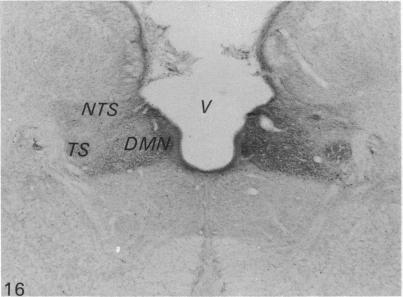

The quantitative cell count showed the presence of about 20,000 ganglion cells with associated satellite elements in the nodose ganglion in the monkey. Among these closely packed cells, at least one-third were substance P (SP) immunoreactive, ranging from faint or moderate to intense staining. Substance P immunoreactivity (SP-IR) was localised in the cell bodies and their long extending neurites. Ultrastructural study showed that SP-IR was not associated with any particular organelles or inclusions. A striking feature of the nodose ganglion was the occurrence of SP-positive pericellular arborisations associated with about 0.5% of the ganglion cells which were almost exclusively SP-negative. The pericellular arborisation displayed diverse morphological forms from a simple tortuous fibre to complex glomerular networks or plexuses encircling the soma of SP-negative ganglion cells. The varicose nerve fibres forming the pericellular arborisations appeared to terminate as 'boutons' contacting the soma of the ganglion cells. Electron microscopic study demonstrated the close spatial relation between the SP-IR profiles and the ganglion cell but there was no direct synaptic contact. In some instances, the SP-IR profiles containing agranular and dense-cored vesicles penetrated the cytoplasm of satellite cells, almost reaching the surface of the soma of the ganglion cell. The sources of origin of the nerve plexuses in the pericellular arborisation were either from the small and sparsely distributed jugular ganglion cells which were intensely SP-IR or from the intrinsic SP-IR nodose ganglion cells. The possibility that the efferent neurons in the dorsal motor nucleus of the vagus could also contribute to the pericellular arborisation was also considered. The function of the pericellular arborisations may be related to the modulation of the SP-deficient ganglion cells with which they associate through the release of SP and probably by way of the satellite cells.

定量细胞计数显示,猴子的结状神经节中存在约20,000个神经节细胞及相关的卫星细胞。在这些紧密排列的细胞中,至少三分之一对P物质(SP)呈免疫反应性,染色强度从微弱、中等至强烈不等。P物质免疫反应性(SP-IR)定位于细胞体及其长延伸的神经突。超微结构研究表明,SP-IR与任何特定的细胞器或内含物无关。结状神经节的一个显著特征是,约0.5%的神经节细胞周围出现SP阳性的树枝状分支,而这些神经节细胞几乎完全为SP阴性。细胞周围的树枝状分支呈现出多种形态,从简单的曲折纤维到复杂的肾小球样网络或围绕SP阴性神经节细胞胞体的丛状结构。形成细胞周围树枝状分支的曲张神经纤维似乎以“终扣”的形式终止于与神经节细胞胞体接触处。电子显微镜研究显示,SP-IR结构与神经节细胞之间存在紧密的空间关系,但没有直接的突触联系。在某些情况下,含有无颗粒和致密核心小泡的SP-IR结构穿透卫星细胞的细胞质,几乎到达神经节细胞胞体表面。细胞周围树枝状分支中的神经丛来源要么是来自强烈SP-IR的小而稀疏分布的颈静脉神经节细胞,要么是来自结状神经节内源性的SP-IR细胞。迷走神经背运动核中的传出神经元也可能参与细胞周围树枝状分支形成的可能性也被考虑在内。细胞周围树枝状分支的功能可能与其通过释放SP并可能通过卫星细胞对与之相关的SP缺乏神经节细胞的调节有关。